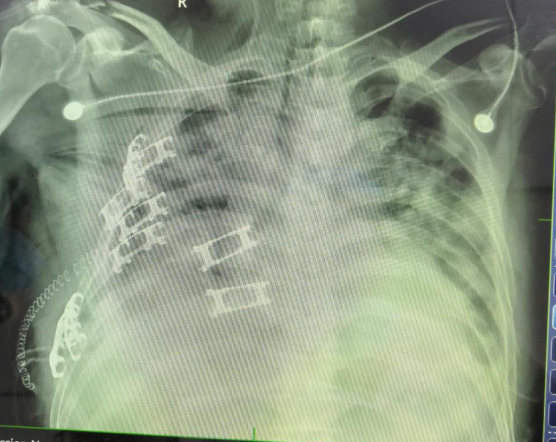

5月6日,馬鞍山市人民醫(yī)院重癥醫(yī)學(xué)科收治一例車(chē)禍傷患者,該患者68歲,車(chē)禍致失血性休克、多發(fā)肋骨骨折、連枷胸、肺挫傷,肝破裂。入院后急診行肝破裂修補(bǔ)術(shù)。術(shù)后患者生命體征仍難以維持,雙側(cè)胸腔放置引流管后,右側(cè)胸腔持續(xù)有血性液體引出,急診行胸腔探查+肋骨內(nèi)固定術(shù),術(shù)后患者出現(xiàn)急性呼吸窘迫綜合征(ARDS),經(jīng)過(guò)ARDS治療策略后依然提示缺氧,出現(xiàn)急性腎損害(AKI),給予床旁連續(xù)腎臟替代治療(CRRT),生命體征在大劑量多巴胺、去甲腎上腺素及腎上腺素支持下仍難以維持。在和家屬充分溝通后,在中大醫(yī)院ICU劉松橋主任的指導(dǎo)下,我院重癥醫(yī)學(xué)科成功放置VA-ECOMO,術(shù)后患者循環(huán)氧合逐漸改善,這也是我院首次開(kāi)展ECMO的治療技術(shù)。